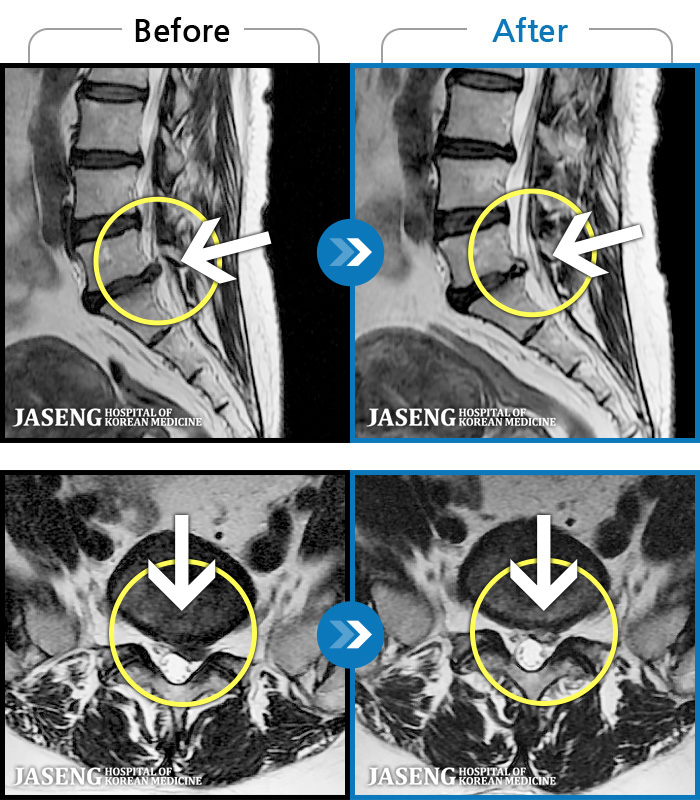

- MRI ġ

MRI ġ

1,299 MRI ũ ʸ Ȯϼ.